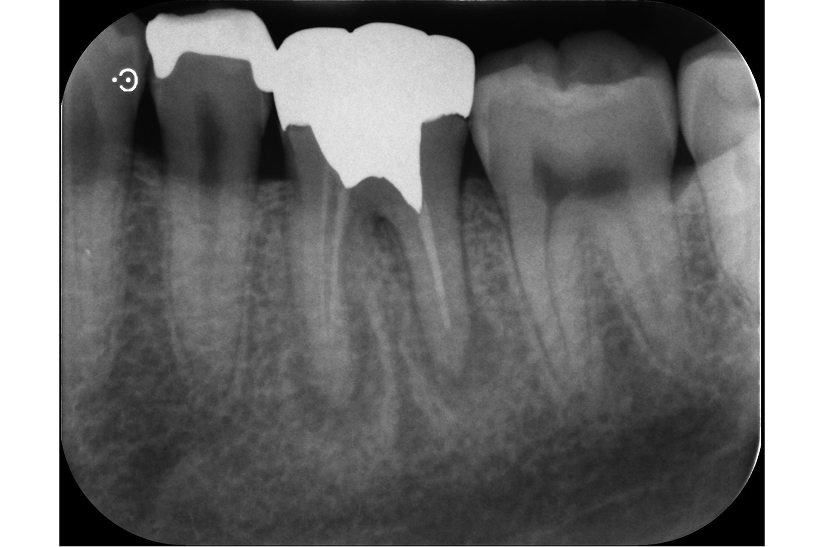

長期予後を見越した根管治療の症例

タップで写真の拡大ができます。

Before

After

主訴

症状はないが、治療が必要な箇所があればしっかり治療しておきたい。

治療内容

イニシャルトリートメント(根管治療・大臼歯)、ファイバーポストコア、セラミッククラウン

治療期間

3ヶ月

治療費用

352,000

治療の

リスク

根尖部透過像が完全に消失しない可能性があります。